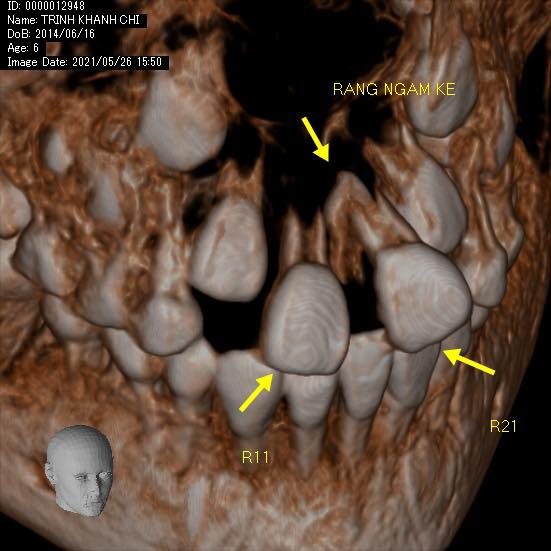

BN đến với than phiền từ bố mẹ rằng hai răng cửa vĩnh viễn của con mọc lên mỗi bạn xoè ra một hướng khác nhau ko ai chịu gặp ai.

Nếu nguyên nhân chỉ là phanh môi bám thấp thì phương án giải quyết lại nhẹ nhàng hơn hẳn. Nhưng ẩn sâu sau màn mưa mà mắt thường không thể nhìn thấy là một bạn răng thừa ngầm mọc lộn ngược giữa kẽ hai răng 11 và 21 làm tách đôi chúng ra. Và nếu không chẩn đoán đúng thì dù có đưa phanh môi về vị trí bám đúng thì chúng mãi mãi cũng vẫn chưa thể gặp nhau được.

Điều đáng nói ở đây là sự quan tâm của bố mẹ đã phát hiện sớm vấn đề của con trước khi nó quá trầm trọng. Sự dũng cảm, hợp tác và hiểu chuyện của một cô bé 7 tuổi làm bác sĩ quá sức bất ngờ.

Thương con gái, lo lắng con bị đau sau quá trình hậu phẫu. Nhưng cuối cùng thì hai bác cháu ta đã chiến thắng bạn răng xấu xí để lớn còn đi thi hoa hậu con gái nhỉ 👍🏻👍🏻👍🏻👍🏻💙👧🏻